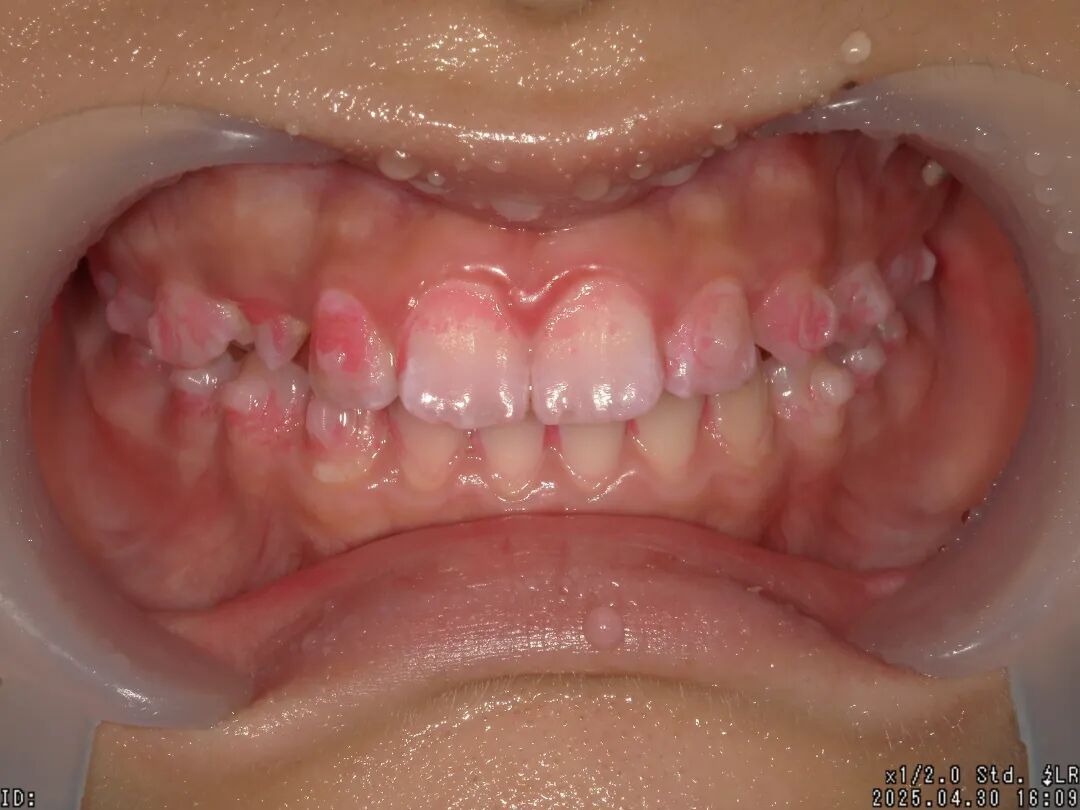

①检查口腔情况 ②拍治疗前口内照片 ③牙菌斑染色

④拍染色后口内照片 ⑤洁牙 ⑥抛光